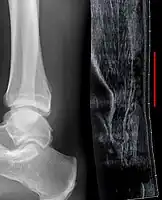

Musculoskeletal ultrasonography can be used to determine the tendon thickness, character, and presence of a tear. It works by sending extremely high frequencies of sound through the body. Some of these sounds are reflected back off the spaces between interstitial fluid and soft tissue or bone. These reflected images can be analyzed and computed into an image. These images are captured in real time and can be very helpful in detecting movement of the tendon and visualising possible injuries or tears. This device makes it very easy to spot structural damages to soft tissues, and consistent method of detecting this type of injury. This imaging modality is inexpensive, involves no ionizing radiation and, in the hands of skilled ultrasonographers, may be very reliable.

Achilles tendon rupture -

Achilles tendon rupture seen on ultrasound. Note discontinuity over several centimeters (red line). No fracture or avulsion (radiograph).